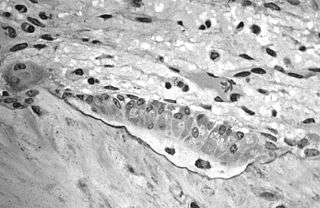

![]() A scanning electronic micrograph of bone at 10,000x magnification. | |